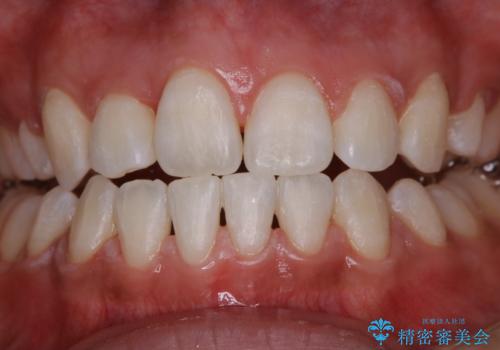

- 数年ぶりに歯科へ来院とのこと。全体的に歯のクリーニングをしてほしいとのことでした。

PMTC60分コースを行いました。

PMTCを行うことにより、スッキリと爽快感が得られたり、見た目も清潔感のある状態になるため、今後の治療などお口に対するモチベーションUPにも繋がります。